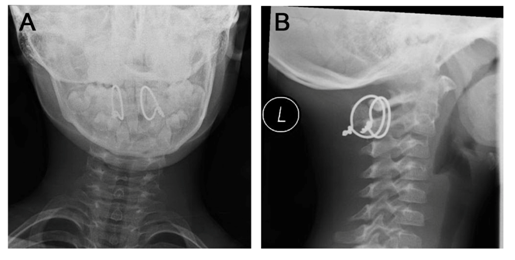

Throughout his stay on the ward, the patient remained neurologically intact, suffered no complications and was dismissed pain free after 8days (Figure 4). After six weeks of immobilization with three weeks each in a Miami-J-collar and a soft collar, the boy had regained good range of motion and was free of pain with no neurologic disabilities. Roentgen graphic controls showed no dislocation (Figure 5) and good functional results. Three month after trauma, the range of motion was flexion/extension 40/0/35°, lateral bending left/right 40/0/40° and rotation left/right 80/0/80°. The tension wires were removed six month after fusion without complications (Figure 6). Another four weeks later the range of motion was flexion/extension 70/0/80° with no chin-to-sternum-distance left, lateral bending left/right 70/0/70° and rotation left/right 80/0/90° (Table 1).

Figure 6 Lateral view x-ray before and after removal of tension wires. A) Before removal, 3month after trauma. B) After removal, with an 8-mm drain in situ.